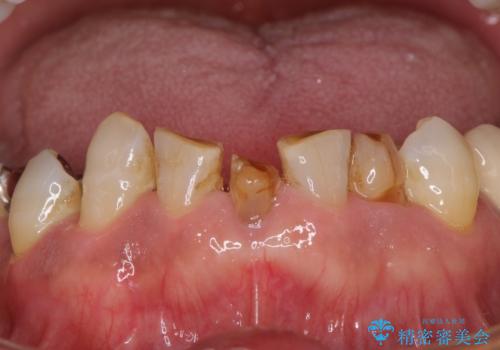

- 乳歯や矮小歯が多くある前歯部の審美障害が気にして来院された患者様です。

上顎の矮小歯は隙間が多く、歯軸の傾斜も大きかったため、部分矯正により補綴治療前に歯の位置を整えることとしました。

下顎の乳歯は支台歯として機能することは困難と思われたので、事前に抜歯をし、上顎の矯正治療終了のタイミングに合わせて、セラミックブリッジにて補綴治療することとしました。

前歯部はディープバイトという、上顎前歯が下顎前歯に深く覆い被さる咬合であったので、理想的には全顎矯正が必要となりますが、今回は患者希望により前歯部のみの部分矯正で対応しました。そのため下顎犬歯の神経を取り除くことになってしまったのは心残りであります。